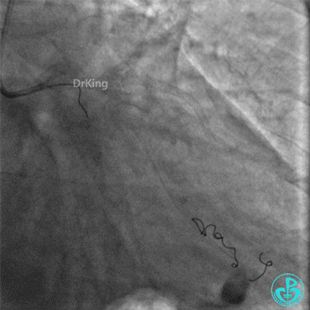

钝缘支分支远端破口完全闭塞。

明胶在血管怎么降解并发症丨前降支CTO同侧逆向开通时侧支血管破裂,弹簧圈联合明胶海绵封堵_https://www.jmylbn.com_新闻资讯_第53张

明胶在血管怎么降解并发症丨前降支CTO同侧逆向开通时侧支血管破裂,弹簧圈联合明胶海绵封堵_https://www.jmylbn.com_新闻资讯_第54张

封堵后观察半小时,患者血压逐步回升,维持在(100~110)/(50~60)mmHg,心率下降至90次/分。